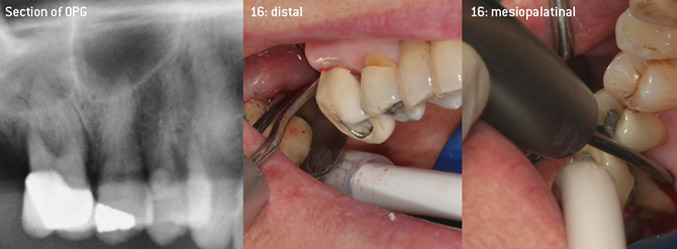

En tant qu'initiateurs du développement du nouvel insert détartreur à air N° 3AP avec un revêtement diamant, les deux dentistes ont reconnu la nécessité d'améliorer les restrictions de manipulation des inserts avec un revêtement diamant disponibles dans le commerce, en particulier lors du traitement des furcations et du travail dans des poches intra-osseuses étroites. Cela devrait être possible pour les procédures non-chirurgicales (figure 2) et chirurgicales (figure 3).

Débridement ouvert des furcations sur les dents 16 et 17

Figure 3 : Débridement ouvert des furcations sur les dents 16 et 17 en cas de perte d'attache avancée

L'objectif était de développer un insert universellement applicable afin d'éviter les changements d'insert qui prennent du temps. En outre, il devrait être plus facile d'utiliser les nouveaux inserts dans les poches intra-osseuses étroites à partir de l'entrée distale et à l'entrée distale de la furcation des molaires maxillaires, ce qui permettrait une utilisation plus efficace des instruments. Pour ce faire, une courbe d'instrument de plus grand diamètre a été utilisée (figure 1), ce qui est très avantageux pour le débridement fermé des dents présentant une perte d'attache avancée et une implication de la furcation en particulier (figure 4).